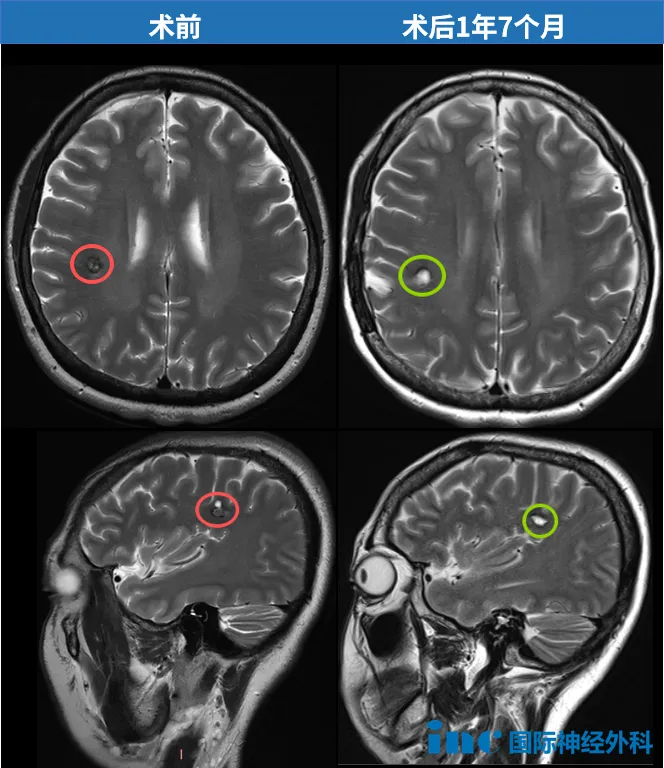

“影像结果非常好,病灶已被完全切除,没有任何副作用。”巴教授在随访中再次让她确定自己已经好了。“下次MRI复查可以至少两年后再做,也就是2027年底。届时我也非常乐意再次为您评估影像。她可以认为自己已经完全从先前的问题中痊愈了!”

时间倒回2024年3月1日。一次体检,却在邓女士的右脑额叶深部,发现了一个约8毫米的海绵状血管瘤。位置较深、紧邻功能区——多位专家给出了一致的建议:“暂不手术,定期观察”。